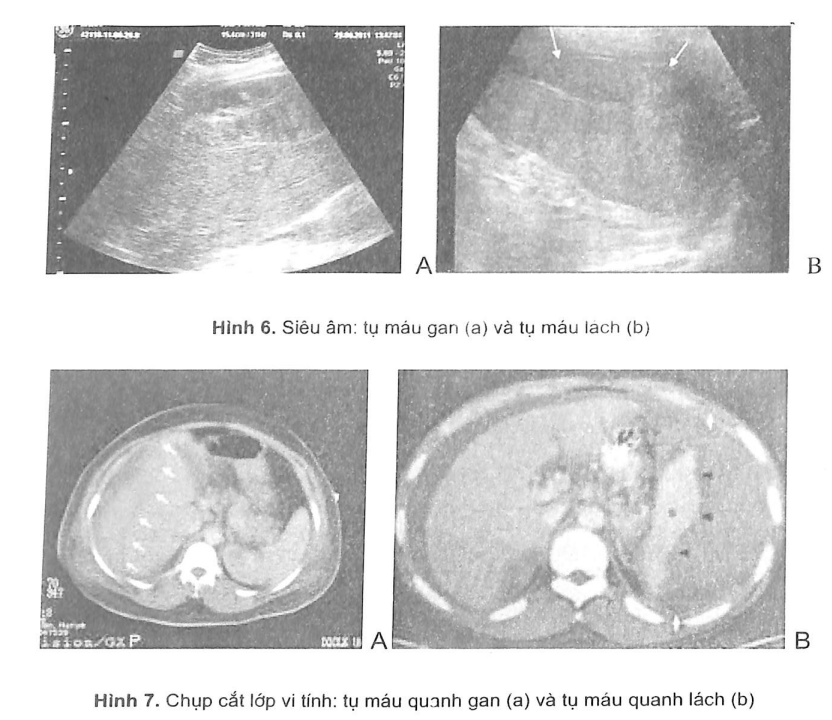

Đối với những trường hợp này, các thăm dò hình ảnh phát hiện các tụ máu dưới bao, tụ máu trong nhu mô (hình 6 và 7) hoặc các tổn thương nhẹ khác là rất có ý nghĩa nhằm tránh tình trạng chảy máu thứ phát.